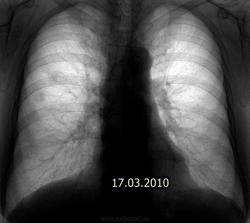

А по снимку от 17.07.09. - показалась гиперплазия правого корня, особенно настораживает тело. В паренхиме - пусто. А вообще, приходится встречаться с такими случаями бурно растущих опухолей, что промежуток в 6 месяцев между флюорографиями пациента не спасает: вот он был (корни не расширены, малоструктурны, паренхима интактна) и вот он пришел (центральный рак, выпирающий по контуру корня с лучистостью и гиповентиляцией верхней доли; на ФБС - карциноматоз трахеи и бронхов, обтурация в\д бронха серой опухолью, цитология - аденокарцинома), а вот через 2 недели его уж и нет на свете (онко:-лечение симптоматическое по месту жительства). Рентгенолог всегда должен быть готов отстоять сою правоту в том, в чем прав.

А по снимку от 17.07.09. - показалась гиперплазия правого корня, особенно настораживает тело. В паренхиме - пусто.

Поламали копья, и будя - на КТ консолидированные переломы 3,4,5 ребер.

Извините, второй снимок 17.03.2010 года.